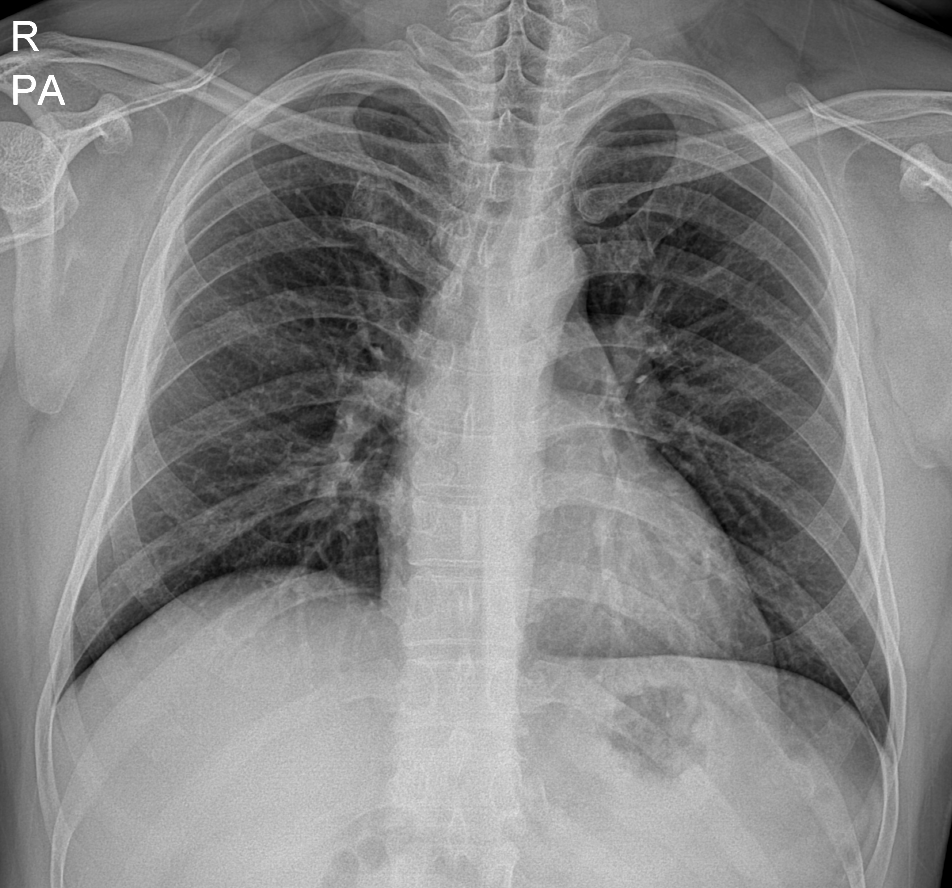

11살 소년

왼쪽부터 오른쪽 상엽으로 퍼진 흉부 X선, 흉부 CT 단면, 종단면